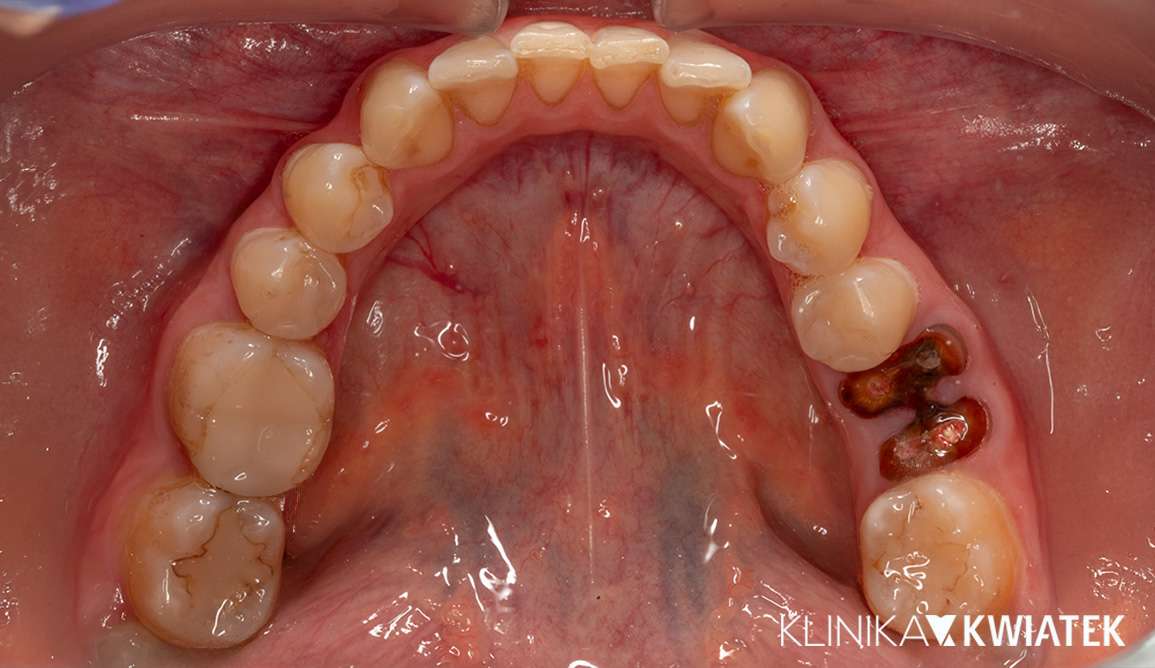

Pani Justyna zgłosiła się do naszej kliniki z problemem braków zębowych oraz koniecznością usunięcia kilku zębów w złym stanie. Dzięki szczegółowej diagnostyce i rozbudowanemu planowi leczenia przeprowadziliśmy serię zabiegów chirurgicznych i implantoprotetycznych, które zakończyły się pełną odbudową uśmiechu. Efektem jest piękny, estetyczny i przede wszystkim funkcjonalny uśmiech, który przywrócił Pacjentce komfort życia.